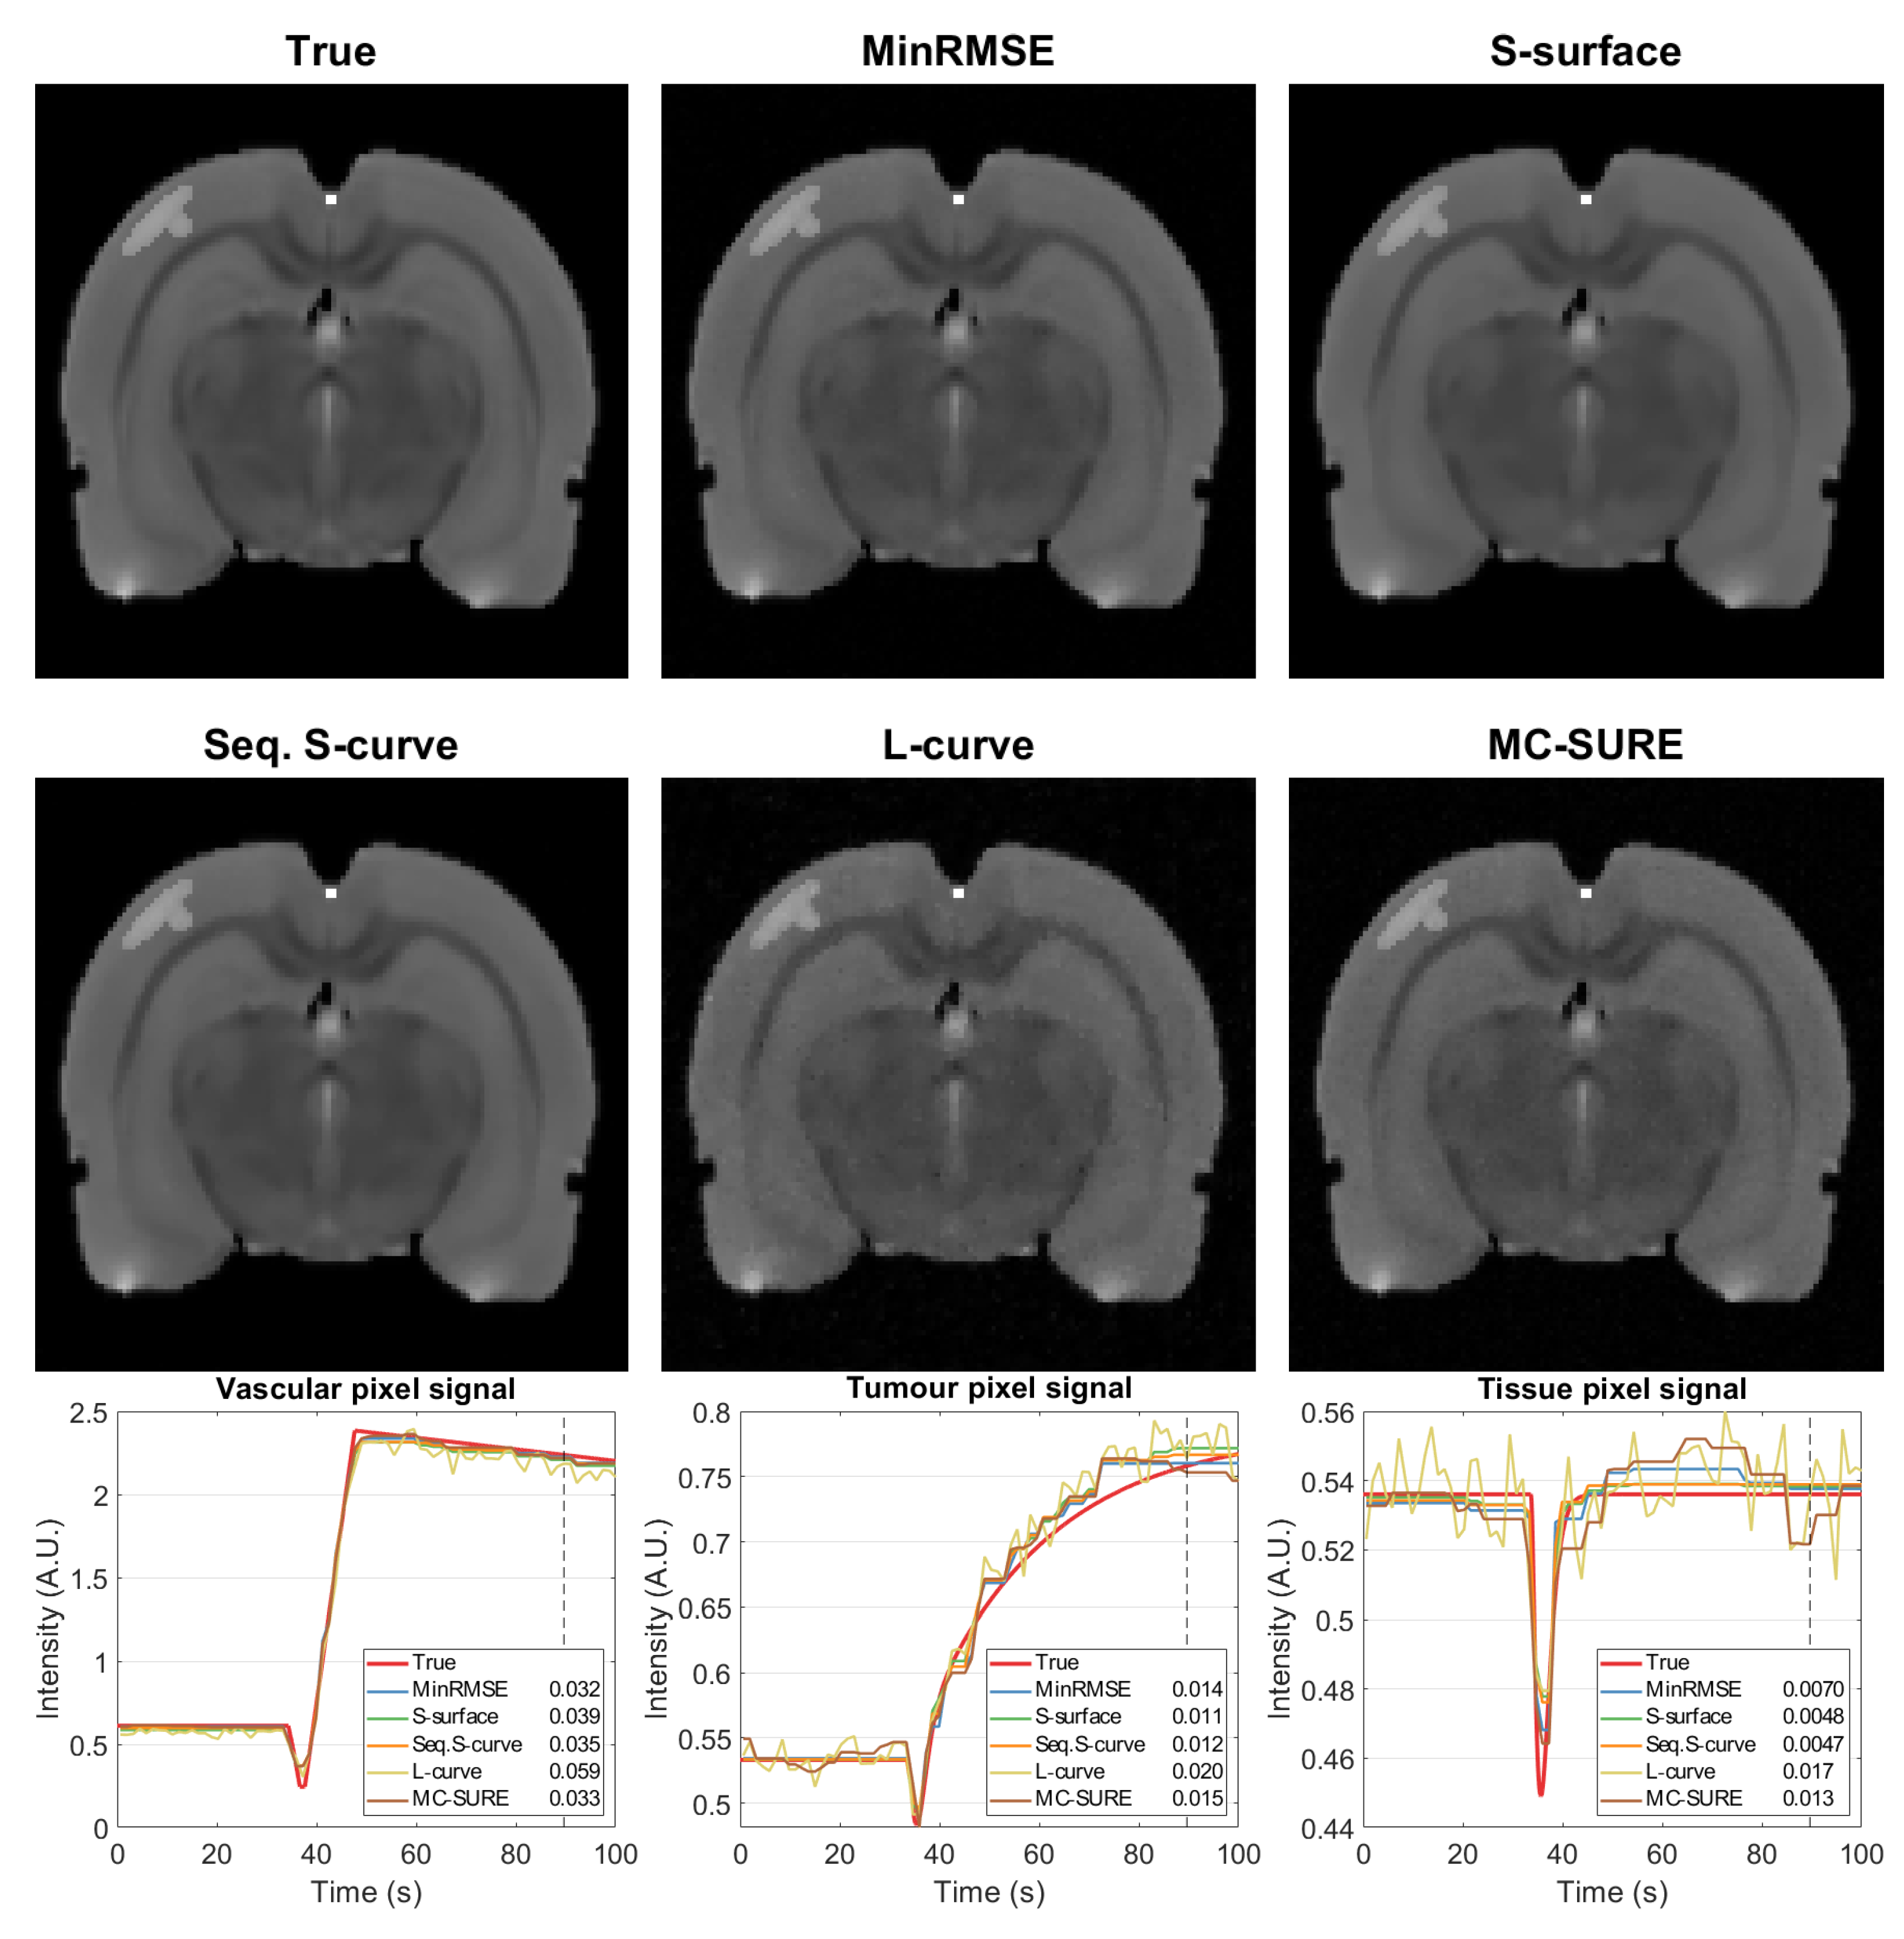

4.2. Experimental Data